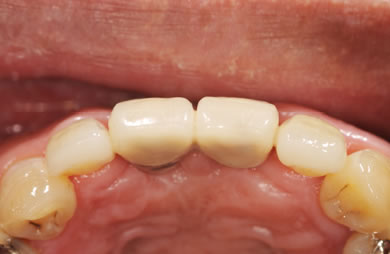

インプラントの症例写真 IMPLANT

骨再生スピードインプラント治療+セラミック治療

| 治療方針 | 審美的・機能的回復をなるべく早くはかる為、抜歯と同時にインプラント治療を行う。また、奥歯に関しては歯周病が進行しているものの、歯の保存が可能な状態である為、エムドゲインを使用し、組織再生をはかる。 | ||||||||||||||||||||||||||||||||

| 治療内容 | インプラント3本(抜歯即日スピードインプラント+GBR)、ハイブリッドセラミック4本、オールセラミックラミネートベニア2本、エムゲドイン組織再生療法 | ||||||||||||||||||||||||||||||||